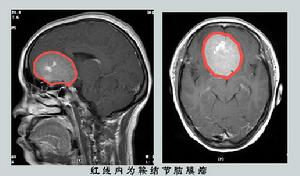

3.頭部MRI(磁共振成像)檢查

TWI為等信號或稍低信號,TWI為高信號或等信號,增強掃描多呈明顯均一強化的鞍上病變,包繞一側或雙側頸內動脈和大腦中動脈,腫瘤以寬基底附著於蝶骨平台、視交叉溝和鞍結節硬膜,可見特徵性的鼠尾征或硬膜尾征。